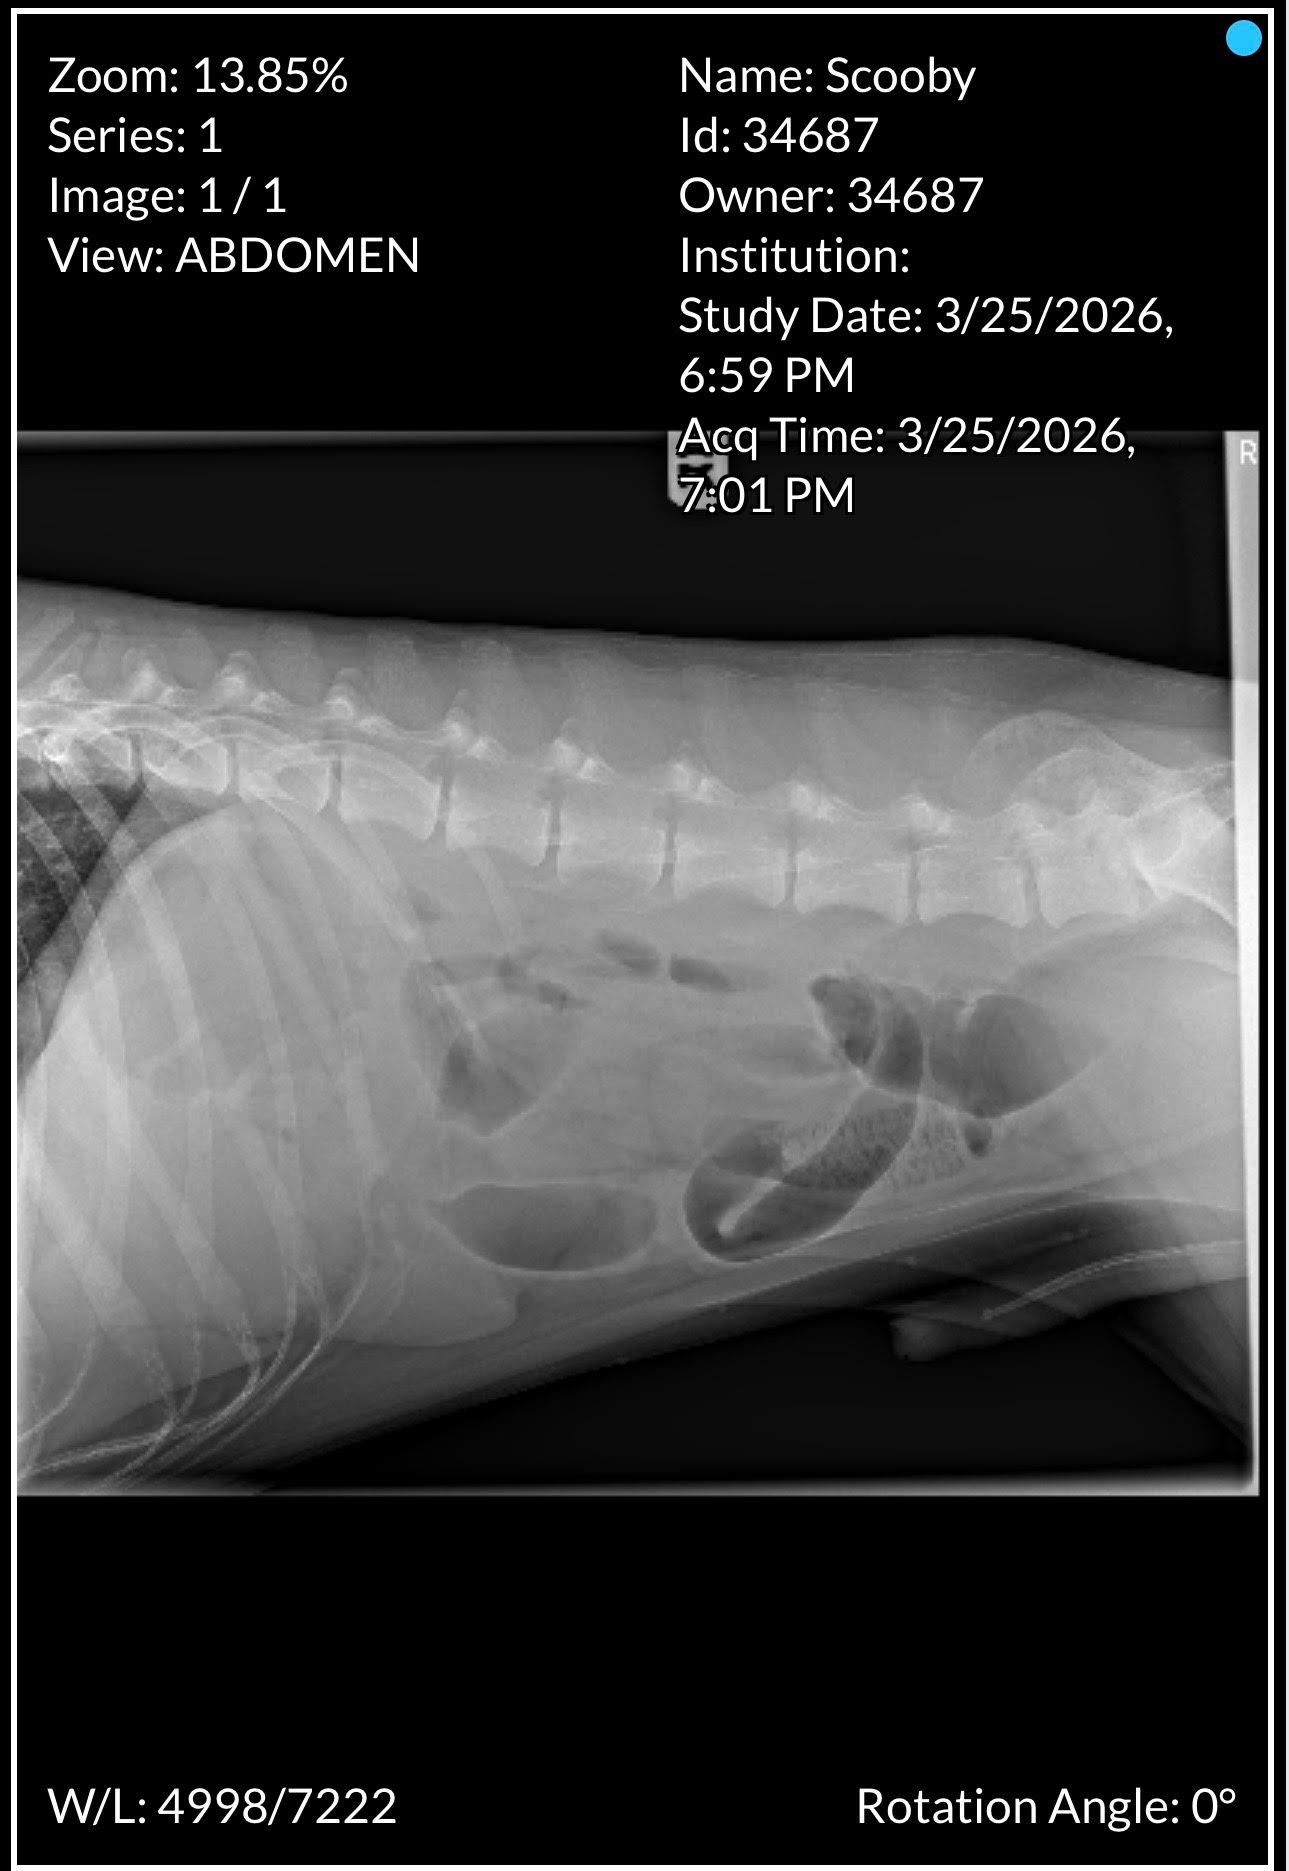

Scooby, my Doberman Pinscher, has been my loyal companion since I rescued him in 2023. He’s truly my best friend, and together we’ve built a bond that means the world to me. Recently, we faced a terrifying situation when Scooby needed emergency surgery for a sudden and life-threatening blockage in his intestines. It was a medical emergency that turned our world upside down and required the removal of three feet of his intestine.